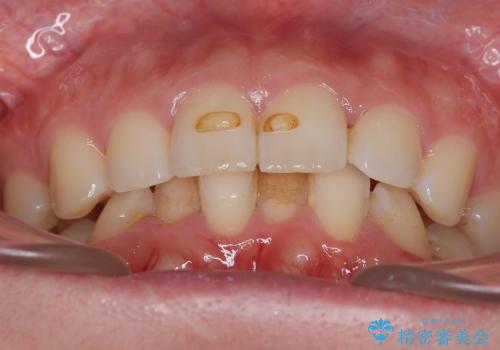

- 下の歯のがたつきを主訴に来院されました。

下の歯のがたつきと右の奥歯の噛みあわせ改善するために治療計画を立てることにしました。

右側臼歯部の咬合改善のために、臼歯部のみ部分的なワイヤー矯正を行い、咬合改善がみられてからインビザラインにて全体的な矯正を行なっていく治療計画を立てました。

ゴム掛けを頑張っていただいたので、噛みあわせも改善され綺麗な歯並びになりました。